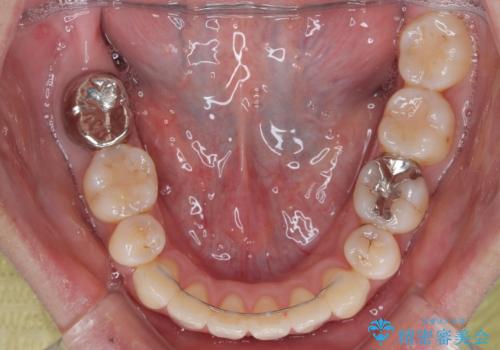

- 矯正装置

- メタルブラケット

- 1年8ヶ月

舌突出癖の改善トレーニングは、仕上がり、治療期間、そして治療後の後戻りに大きな影響を及ぼします。

トレーニングをしっかりと行っていただいたため、スッキリとした口元に仕上がりました。